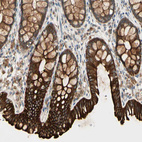

Immunohistochemical staining of human colon shows strong cytoplasmic positivity in glandular cells.